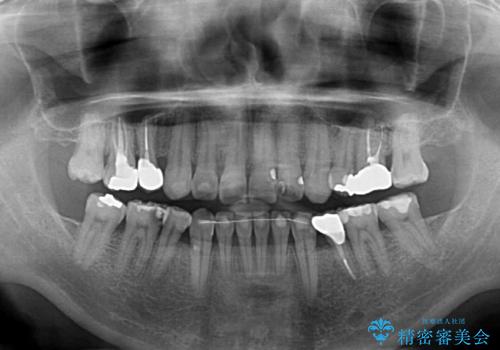

- むし歯による奥歯の痛みを気にして来院された患者様です。

神経にまでむし歯の及んでいる歯や、既に根管治療がされている歯に痛みがあったため、まずは根管治療を行うこととしました。

その後、以前行った抜歯矯正の後戻りをインビザライン・ライトにより改善し、むし歯や銀歯はオールセラミッククラウンにて補綴治療することとしました。